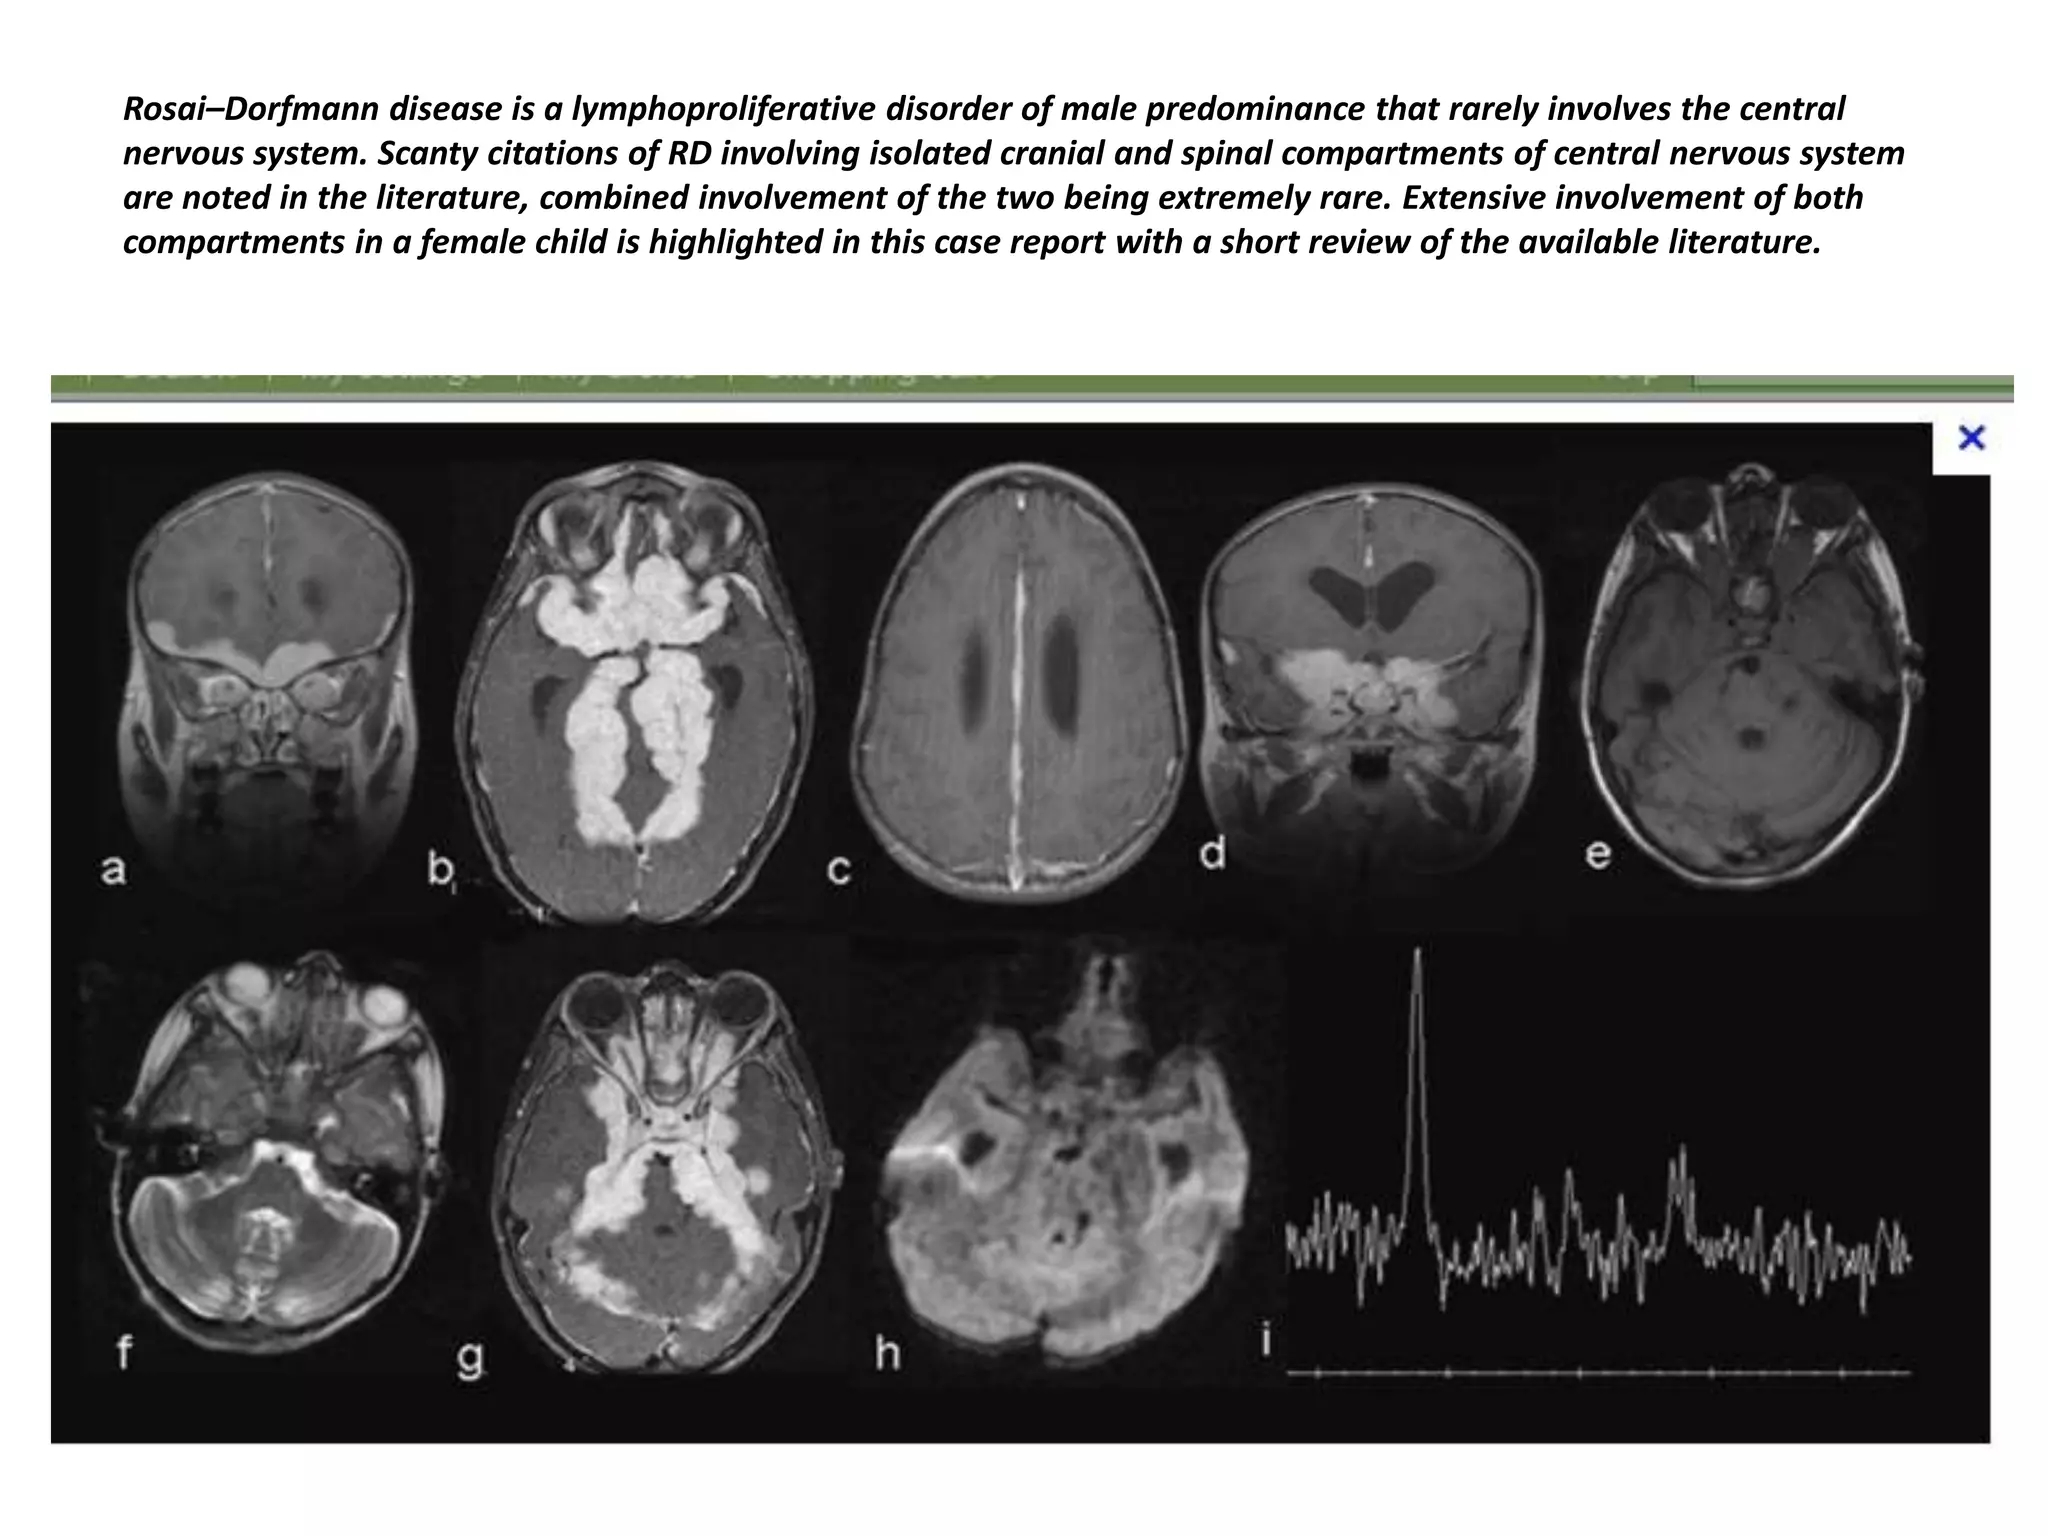

Rosai–Dorfmann disease is a lymphoproliferative disorder of male predominance that rarely involves the central

nervous system. Scanty citations of RD involving isolated cranial and spinal compartments of central nervous system

are noted in the literature, combined involvement of the two being extremely rare. Extensive involvement of both

compartments in a female child is highlighted in this case report with a short review of the available literature.